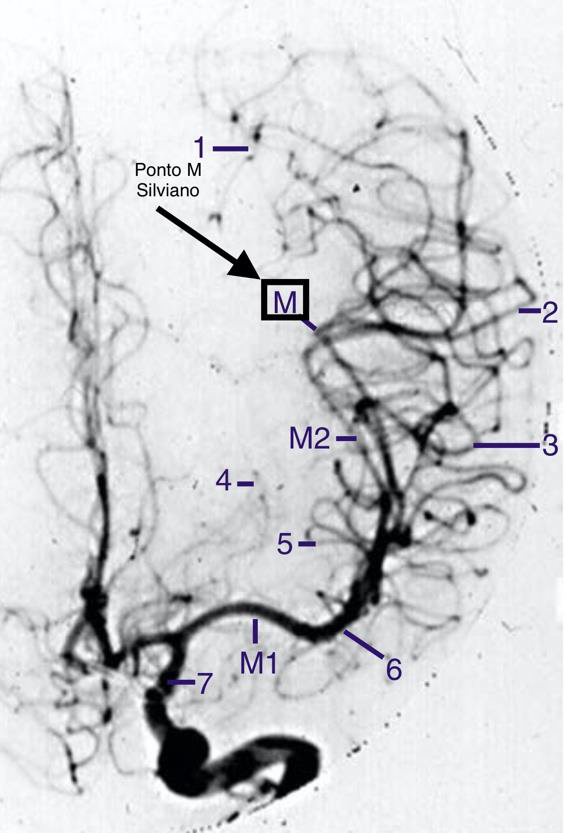

A alça do ramo mais posterior da terceira porção da artéria cerebral média (M3) é chamada de ponto M ou ponto Silviano (vide figura).

A estrutura do parênquima cerebral que o ponto Silviano marca é o giro: